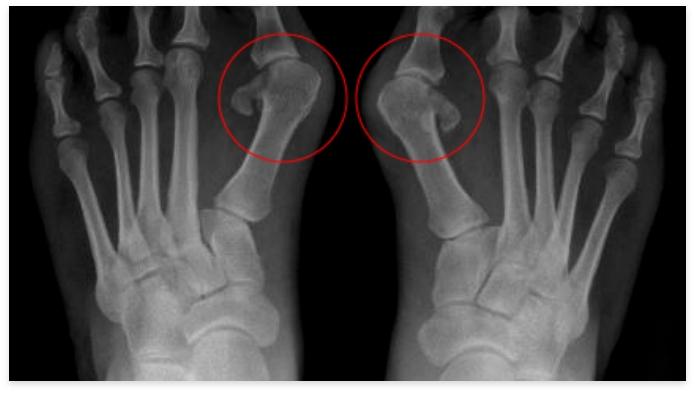

Iatrogenic Hallux Varus

Iatrogenic H. Varus, is a surgeon pitfall, happens when he overcorrects the Hallux Valgus. In this situation, the big toe goes further to outside from a normal angle of 9 degrees, and when you see the foot, the big toe is separated from the other toes. This problem happens, when you underestimate the power of the abductor muscle of the first toe, and when the adductor muscle is anatomized, the big to is retracted to varus by the unopposed abductor muscle. In some cases, the osteotomy is overridden, and the distal part of the osteotomy is lateralized. The surgical solution is to perform a corrective surgery by reverse Scarf operation plus transferring abductor tendon origin to adductor origin. The worst thing a surgeon can do is to perform another Akin osteotomy on the first proximal phalangeal bone because it makes a skew foot deformity or serpentine foot. The other approach is, to use Osteopathic technics, and Orthosis, and to teach the corrective exercises. Osteopathy should reinforce the new attachment of adductor muscle, and release of the abductor. These technics may resolve more than 60% of the surgeon-made deformities. If the deformity is fixed after several years of onset, and painful osteoarthritis or Hallux rigidus appeared, then the surgery will be inevitable, but if the patient doesn’t waste the time, and come in the golden period to an Osteopath, he/she will benefit from Osteopathic technics.